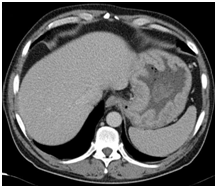

In this instance, a 53 year old Caucasian male with no significant past medical history presented to his primary care provider with a 2 week history of shortness of breath on exertion. Physical exam was unremarkable. Routine bloods revealed a Hemoglobin of 6 g/dL (13-17g/dL) with an MCV of 64 fL (80-100fL). Iron studies confirmed an iron deficiency anaemia. Other notable lab values included serum albumin 1.9 g/dL (3.5-5.0g/dL) with no proteinuria. CT Imaging of the thorax, abdomen and pelvis revealed a grossly dilated stomach, with diffuse circumferential wall thickening, measuring up to 3cm in maximum diameter (Figure 1). It also revealed extensive bilateral 2nd order pulmonary emboli and a large IVC clot extending from the level of the renal veins to the common iliac veins (Figure 2).

Figure 2CT image with IVC thrombus.